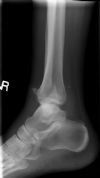

Bimalleolar Ankle Fracture 2/6:: Pre-reduction. Lateral radiograph